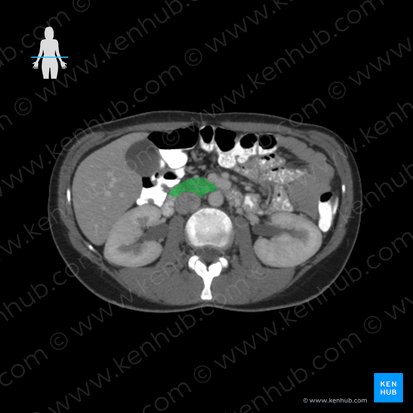

Le pancréas est un organe allongé d’environ 15 cm qui se trouve obliquement le long de la paroi abdominale postérieure, plus précisément au niveau des vertèbres L1 et L2. Dans un contexte clinique, sa position oblique rend impossible l’observation de l'ensemble de ses parties dans une seule coupe transversale. Le pancréas entre en contact avec plusieurs structures avoisinantes puisqu’'il traverse les régions épigastriques, l'hypochondre gauche, et une petite portion de la région ombilicale de l'abdomen.

À l'exception de la queue, le pancréas est situé dans l'espace rétropéritonéal de la cavité abdominale, c'est-à-dire derrière le péritoine. Si l'on cherche à illustrer l'emplacement de cet organe, un schéma du pancréas serait idéal pour mettre en évidence ces relations anatomiques, soulignant ainsi le rôle crucial du pancréas dans le fonctionnement de notre organisme.

Comme vous avez maintenant une meilleure compréhension de la localisation du pancréas, il est temps d'explorer son anatomie. Sur un schéma du pancréas, on remarque que cet organe parenchymateux est divisé en cinq parties anatomiques : la tête, le processus unciforme, l’isthme (col), le corps et la queue.